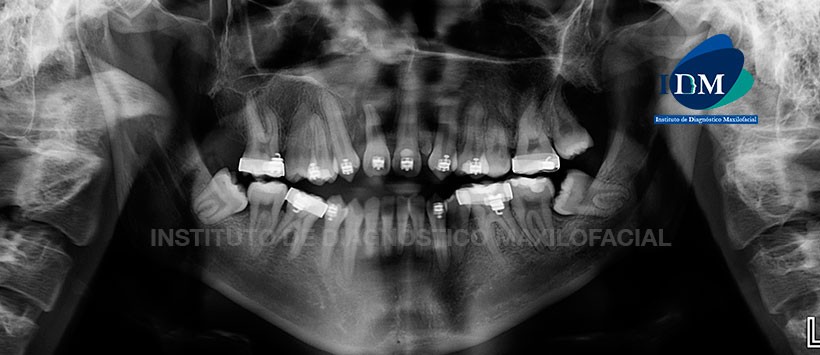

A la evaluación de la radiografía panorámica se aprecia aparatología para ortodoncia fija en múltiples piezas, ausencias de piezas dentarias, pieza 38 y 48 impactadas en posición mesioanguladas. Siendo lo mas resaltante la presencia de un diente supernumerario localizado entre las piezas 21 y 23, así mismo se observa una fisura palatina unilateral de lado derecho, localizada entre las piezas 11 y 13. (Figura 1)